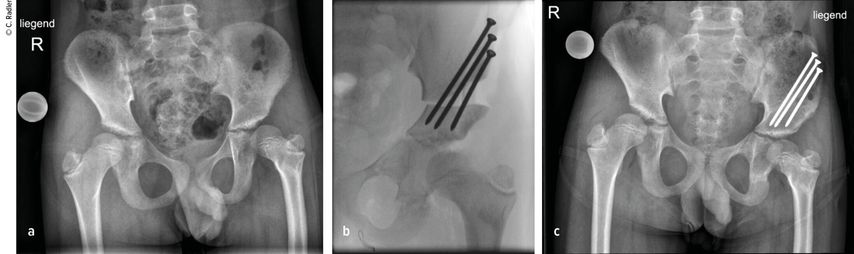

Im Rahmen dieser Operation können auch die Retrotorsion und der Schenkelhalsvarus korrigiert werden. Eine Verlängerung bei nicht optimal überdachter Hüfte führt meist zu einer Subluxation oder Luxation, was eine schwerwiegende Komplikation darstellt, die nur schwer und meist nicht folgenlos zu beheben ist. Auch bei älteren Patienten ist die Überdachung vor einer eventuellen Verlängerung zu überprüfen, wobei besonders ab dem 4. Lebensjahr eine Tripelosteotomie eine bessere Überdachung und Einstellung der Pfanne gegenüber einer Acetabuloplastik erlaubt (Abb.2).

Abb. 2:Versorgung eines kurzen Pfannendachs mittels Tripelosteotomie, um die Hüfte während der Verlängerung vor (Sub-)Luxation zu schützen